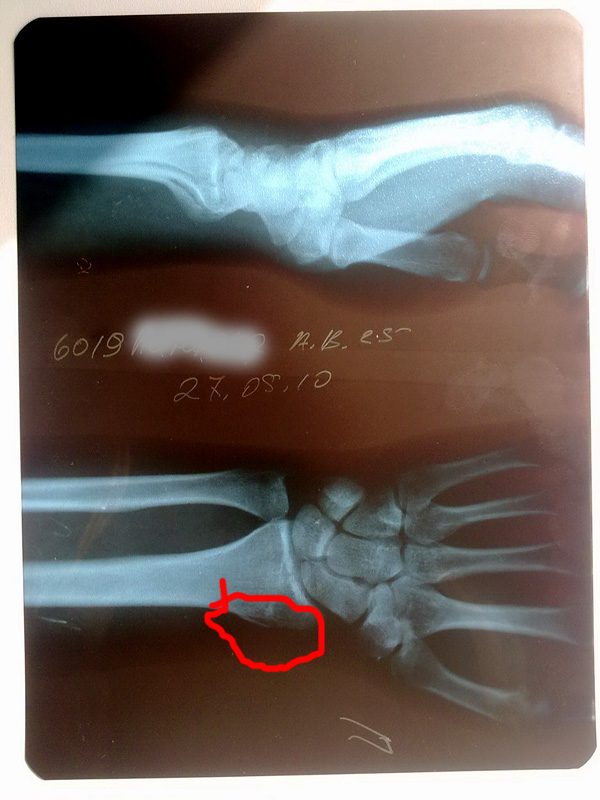

Breaking News

1.jpg [ 162.89 Кб | Просмотров: 340 ]

2.jpg [ 109.64 Кб | Просмотров: 359 ]

пычатать многа не могу

Кстати рентген они снимали на материалы Kodak.

Кстати, не понял, зачем они обе руки рентгенили, если перелом только на одной? :shock:

upd: уже допёр, что это одна и та же рука. :D